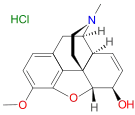

6-Acetyldihydromorphine hydrochloride 6-Acetyldihydromorphine hydrochloride |